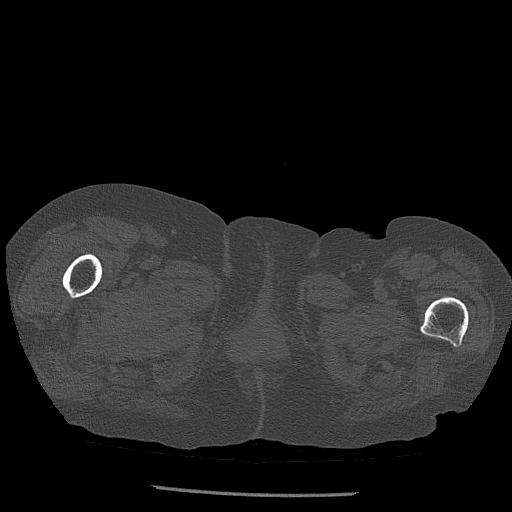

102803 1/12(キウスなし) 1/27 左下腿 4R 30歳女性 左脛骨軸内釘